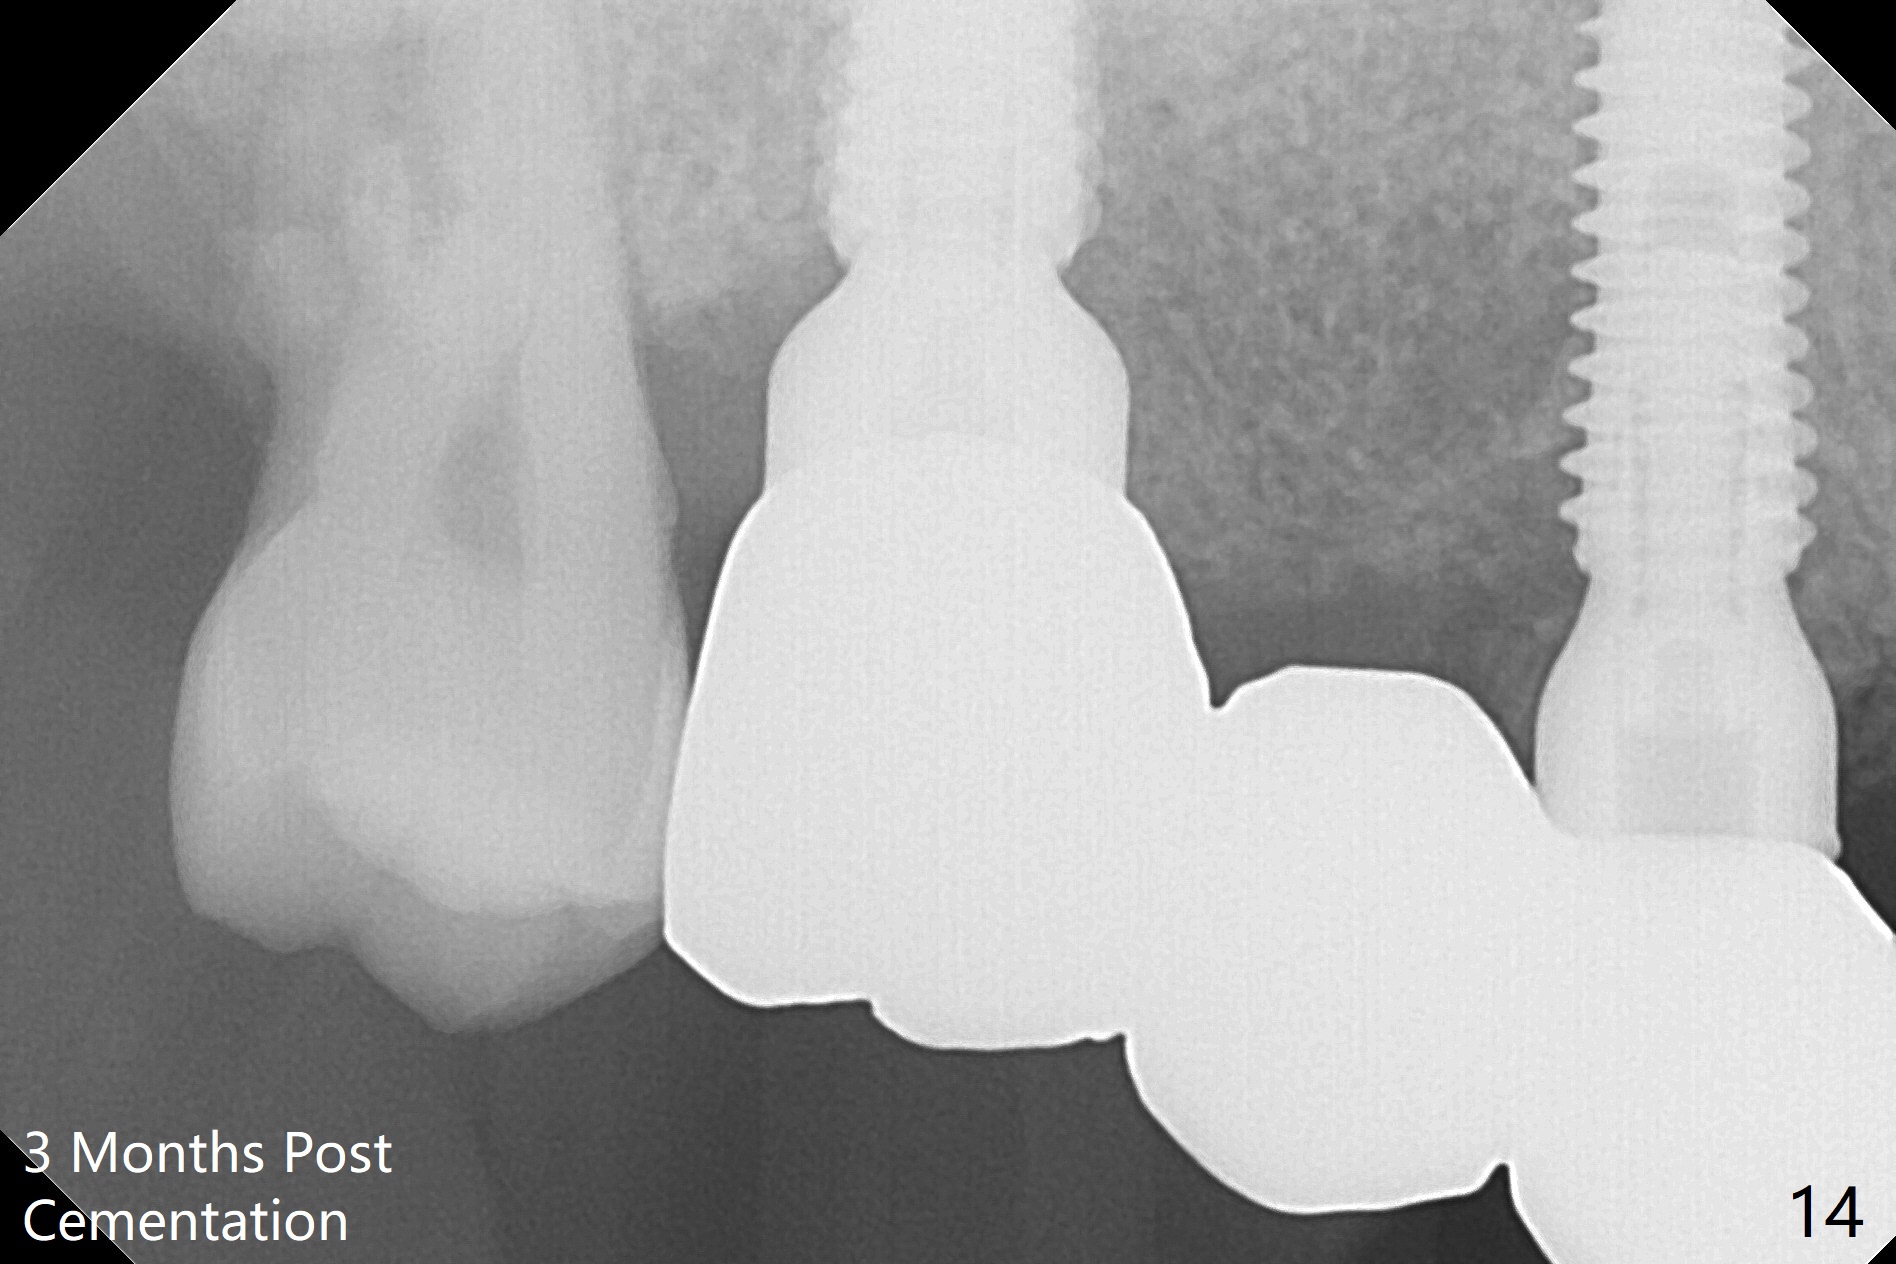

The 36-year-old man (ex-smoker, quit for 4-5 years) insists upon #3 and 5 extraction first for implants, in spite of more severe infection at #7, 14,19,30 (Fig.1-4). The gingiva around #23-26 implants is healthy 3 weeks postop (Fig.5). The initial depths at #3 and 5 are 8.5 mm (bone-level) and 18 mmm (gingiva-level (13 mm (implant length) + 5 mm cuff), respectively. When a drill penetrates the sinus floor, confirm the depth. After use of 3.8 mm drill, 4.5 mm tap drill is inserted at #3 without stability, while a 4.5x13 mm implant is placed at #5 with primary stability (Fig.6,7). Then a 5x11.5 mm is placed at #3 subcrestal proximally after sinus lift with Vanilla graft (without sinus membrane perforation; Fig.8). The implant at #5 is seated ~1 mm deeper (subcrestal mesially (^^); supracrestal distally (^)); allograft is placed around the implants prior to insertion of 6.5x7(5) and 5.5x4(5) mm abutments; last more allograft is added (Fig.9 *, 10). The implants seem to have been osteointegrated 4.5 months postop (Fig.11,12). The gingiva is healthy around the implants without bone loss 3 months post cementation (Fig.13,14).